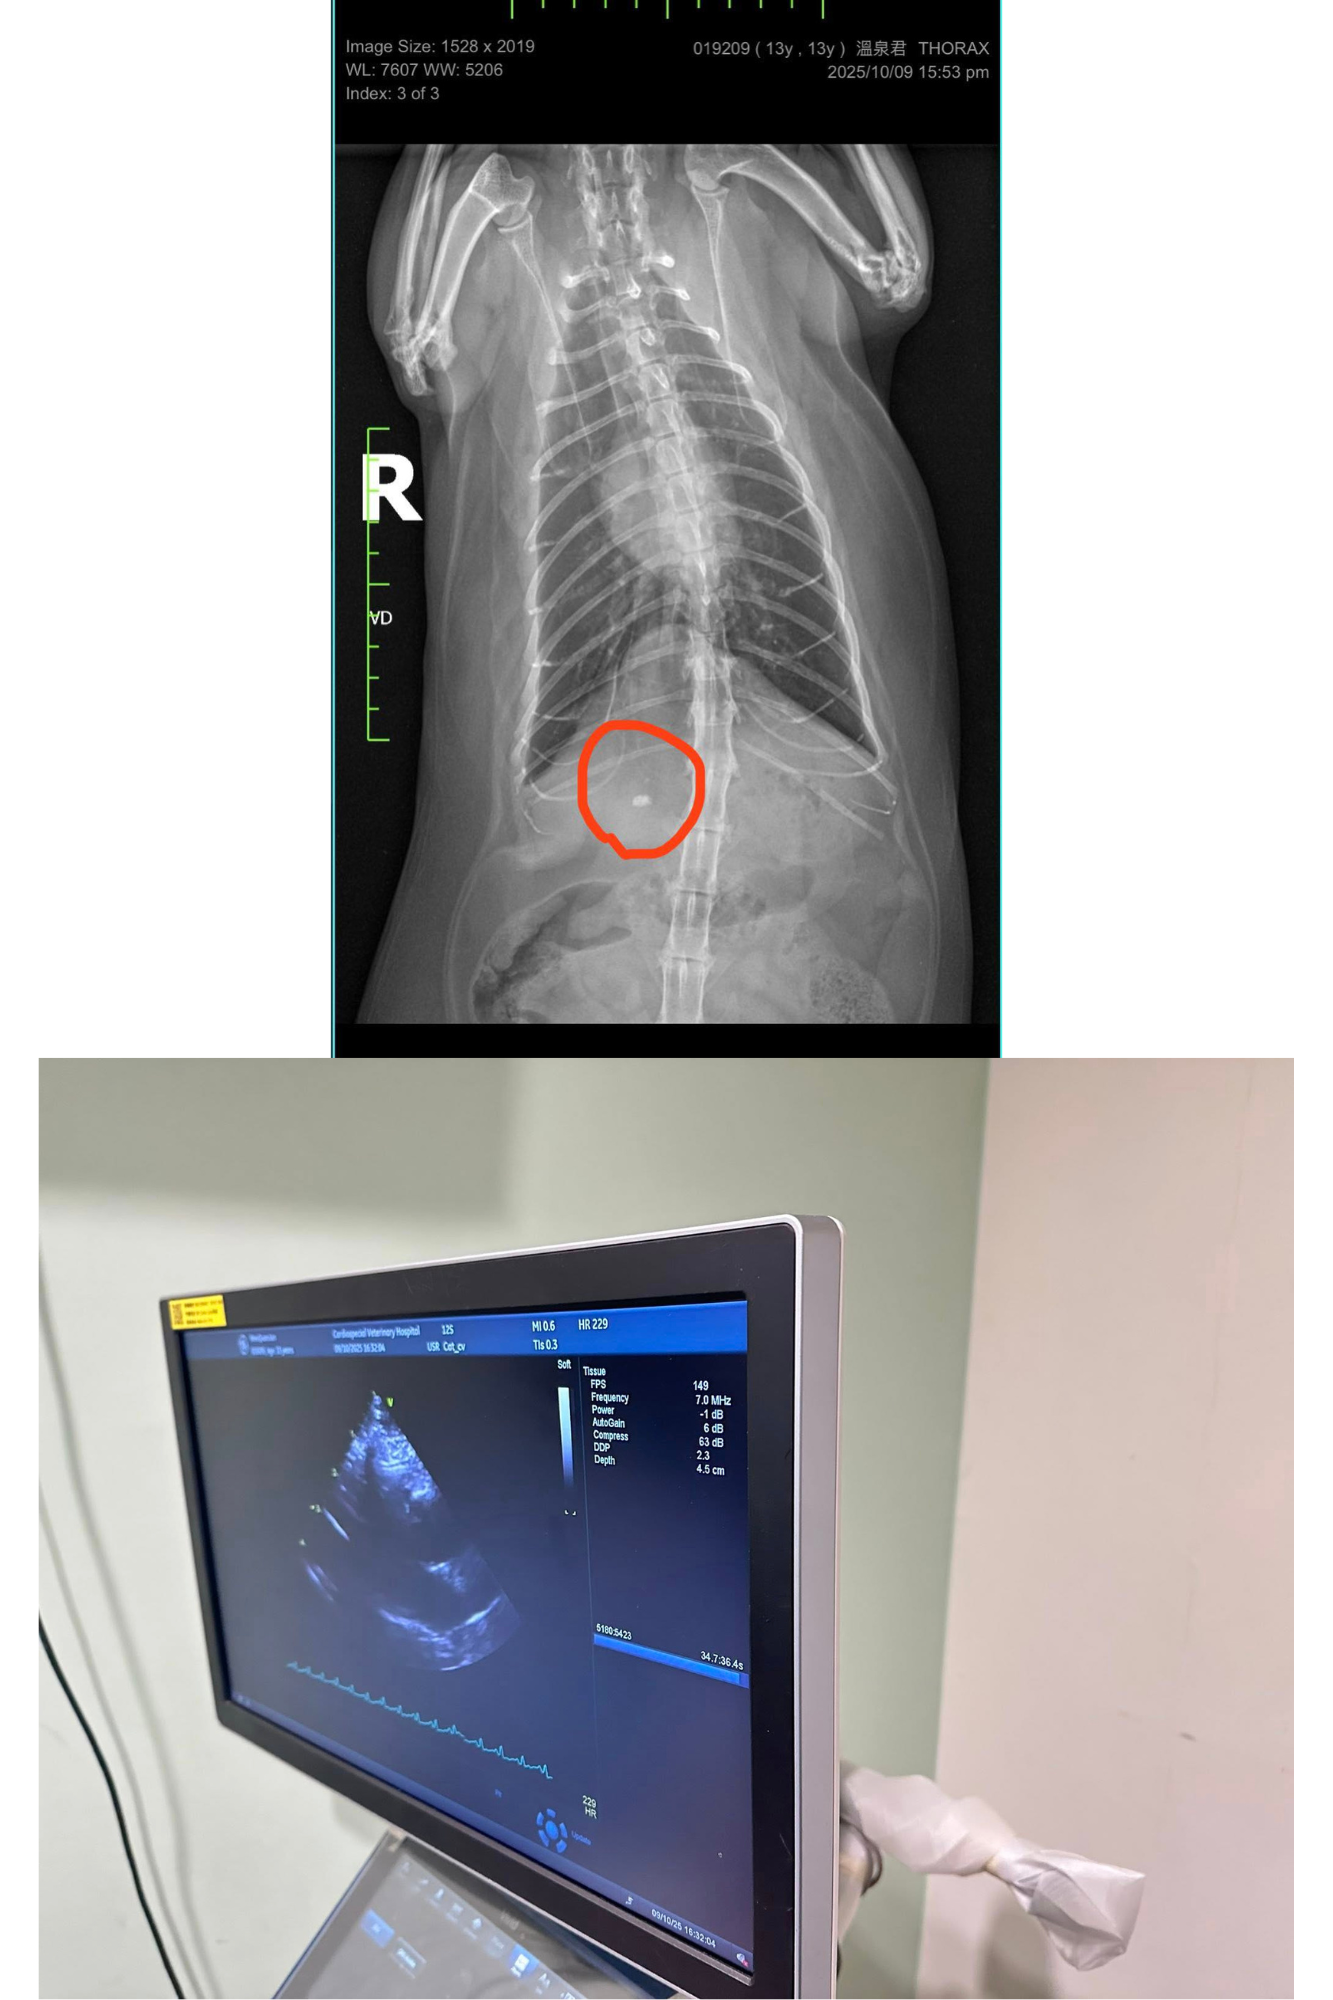

2025年10月9日誌專心醫院進行心臟檢查,今日主要做心臟的X光、超音波檢查、心電圖檢測。血壓正常無明顯心雜音。胸腔X光發現心臟輪廓大小正常,未見肺積水或胸膜積液證據。

右前腹腔影像有一礦物化物質,疑似膽結石,不確定是皮下或腹腔內,但需詳細確認的話,需用超音波檢測。總體來說,溫泉君心臟維持的不錯,無惡化。平時請密切監控心跳與呼吸,請避免過度興奮緊張與任何明顯加快心跳的理由。

2025/10/9 溫泉君 專心回診 陳炫甄醫師

今日主要做心臟的X光、超音波檢查、心電圖檢測。

血壓正常120-130,無明顯心雜音。

胸腔X光發現心臟輪廓大小正常,未見肺積水或胸膜積液證據。

右前腹腔影像有一礦物化物質,疑似膽結石,不確定是皮下或腹腔內。

但需詳細確認的話,需用超音波檢測。

心臟超音波發現左心房大小與三年前相比,一樣是肥厚心肌病,但無明顯變大。屬於B1期。

心電圖的部分,沒有傳導的異常,心跳檢測時有因緊張過快,但並沒有早跳停拍的狀況。

醫師另外建議溫泉君可追蹤甲狀腺濃度的變化。

總體來說,溫泉君心臟維持的不錯,無惡化。

平時請密切監控心跳與呼吸,請避免過度興奮緊張與任何明顯加快心跳的理由。